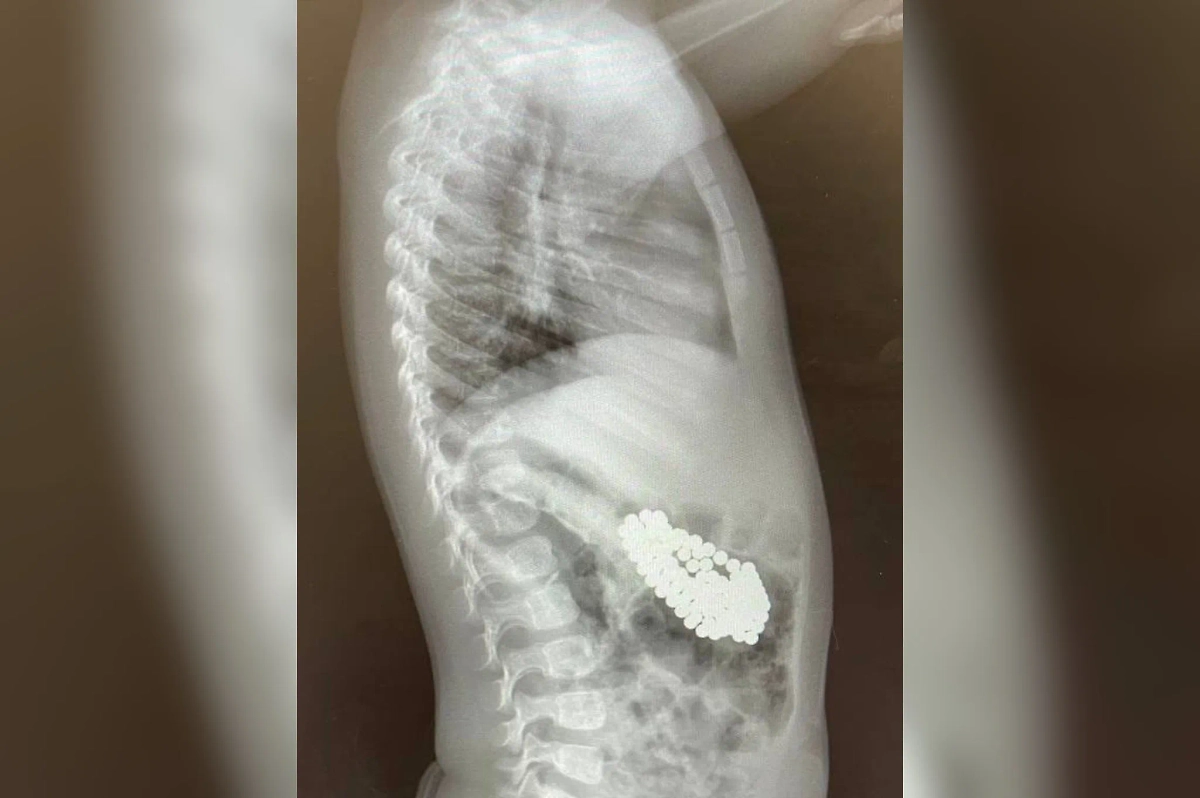

В Подмосковье полуторагодовалый ребёнок смог проглотить 130 магнитов и литиевую батарейку. Мальчика срочно госпитализировали в больницу Подмосковья, где провели ему гастроскопию, рассказал заведующий эндоскопическим отделением Александр Иноземцев.

«Магниты сцепились друг с другом, что привело к повреждению слизистой оболочки и образованию язвы. Действовать нужно было быстро. С помощью специальных инструментов — эндоскопического «Сачка», зажима по типу «Аллигатор» и «Корзины Дормиа» мы провели гастроскопию, в ходе которой последовательно извлекли инородные тела из желудка мальчика. После операции выполнили контрольную рентгенографию и обнаружили ещё 3 магнита, которые невозможно было удалить с помощью эндоскопа», — объяснил врач.

В итоге некоторые магниты начали перемещаться в кишечник, из-за чего было принято решение отправить малыша на новую операцию. Инородные предметы удалось извлечь с помощью лапароскопа и телескопической трубки через маленькие разрезы в брюшной стенке. В итоге все магниты успешно достали, ребёнка уже выписали домой. Сейчас маленький хулиган находится на амбулаторном лечении.